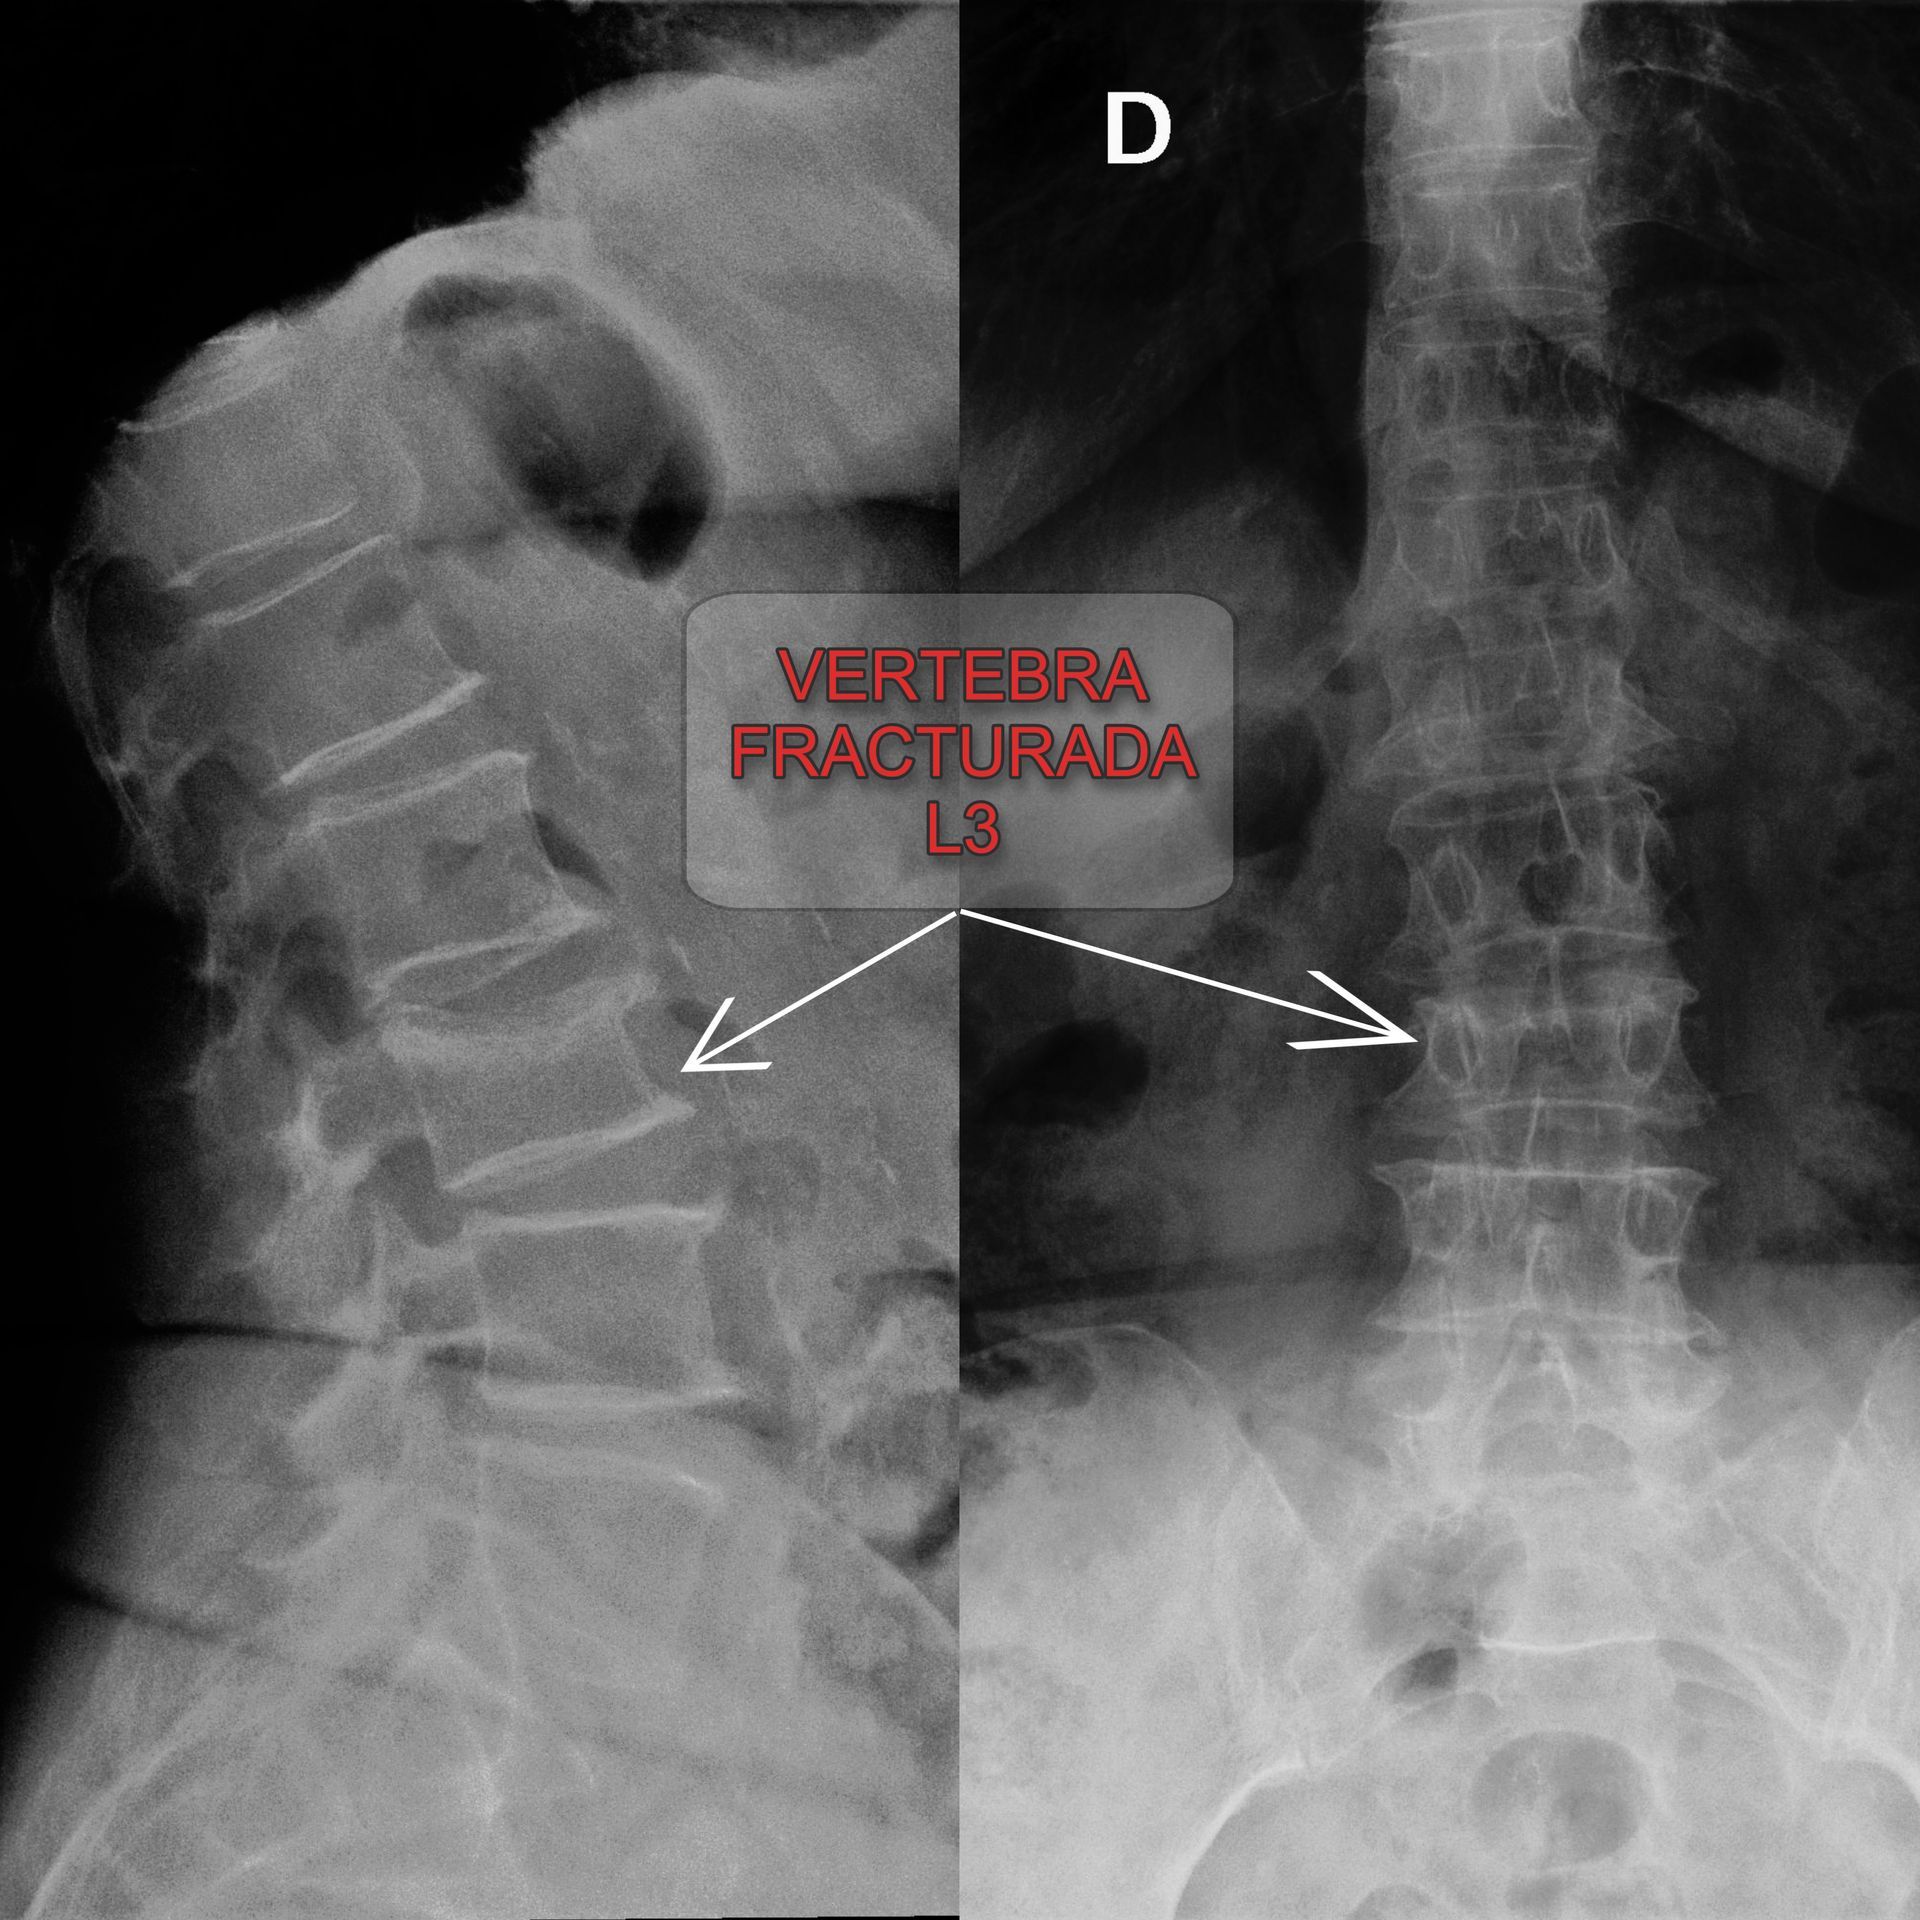

Este procedimiento está indicado para pacientes que presentan fracturas vertebrales dolorosas, especialmente aquellas relacionadas con:

• Lesiones traumáticas: Accidentes o caídas que resultan en fracturas por compresión.

2. Inserción de la aguja: El cirujano introduce una aguja a través de la piel hasta llegar a la vértebra fracturada, guiado por imágenes de rayos X en tiempo real.